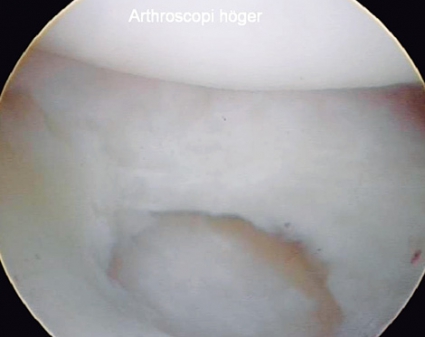

Akuta skafolunära skador fixeras med stift: ett mellan scaphoideum och lunatum och ett mellan scaphoideum och capitatum. Stiftningen görs med fördel artroskopiassisterad så att man ser att stiften hamnar rätt och att det skafolunära intervallet sluts adekvat. Stiften bör sitta kvar i ca 8 veckor medan patienten är gipsad. Om stiftningen görs i akut skede blir slutresultat vanligen gott, men med viss stelhet [1].

För kroniska partiella eller totala skafolunära ligamentskador utan felställning saknas ännu behandlingskonsensus. Att göra någon form av öppen ligamentsutur eller ligamentrekonstruktion understödd av dorsal kapselförstärkning plus stiftning och gips är vanligt. Behandlingen avgörs av faktorer som skafolunära ligamentets kvalitet, skadetyp, skadeutbredning, möjligheterna till korrigering av felställningen och eventuella samtidiga broskskador eller artros. Metoder som artroskopisk »shaving« + värmebehandling (shrinkage) av ligamentet + stiftning samt insättning av ben–ligament–bengraft finns också beskrivna.

• Artroskopifynd: Är haktestet positivt, dvs går disken att lyfta upp med haken underifrån? I så fall tyder det på att det djupa foveala TFCC-fästet är skadat. Är typen av skada sådan att den tillåter reinsertion eller inte?